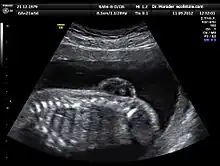

Échographie d'un fœtus de 21 semaines souffrant de spina bifida (la protubérance en haut à droite)

L’échographie est la principale et la plus courante des méthodes de diagnostic prénatal. En France, il est ainsi obligatoire de pratiquer trois examens échographiques[9], à 12, 21, puis 33 semaines d’aménorrhée.

Cette technique permet, grâce à l’utilisation d’ultrasons, de voir le bébé par image de synthèse. Elle permet de contrôler l’avancée de la grossesse et détecte un certain nombre de malformations ou de signes avant-coureurs de maladies génétiques. Par exemple, cet examen est l’un des trois composants du « triple test » en vue du dépistage de la trisomie 21, car il permet la mesure de l’épaisseur de la nuque, signe d’appel de cette affection[10].